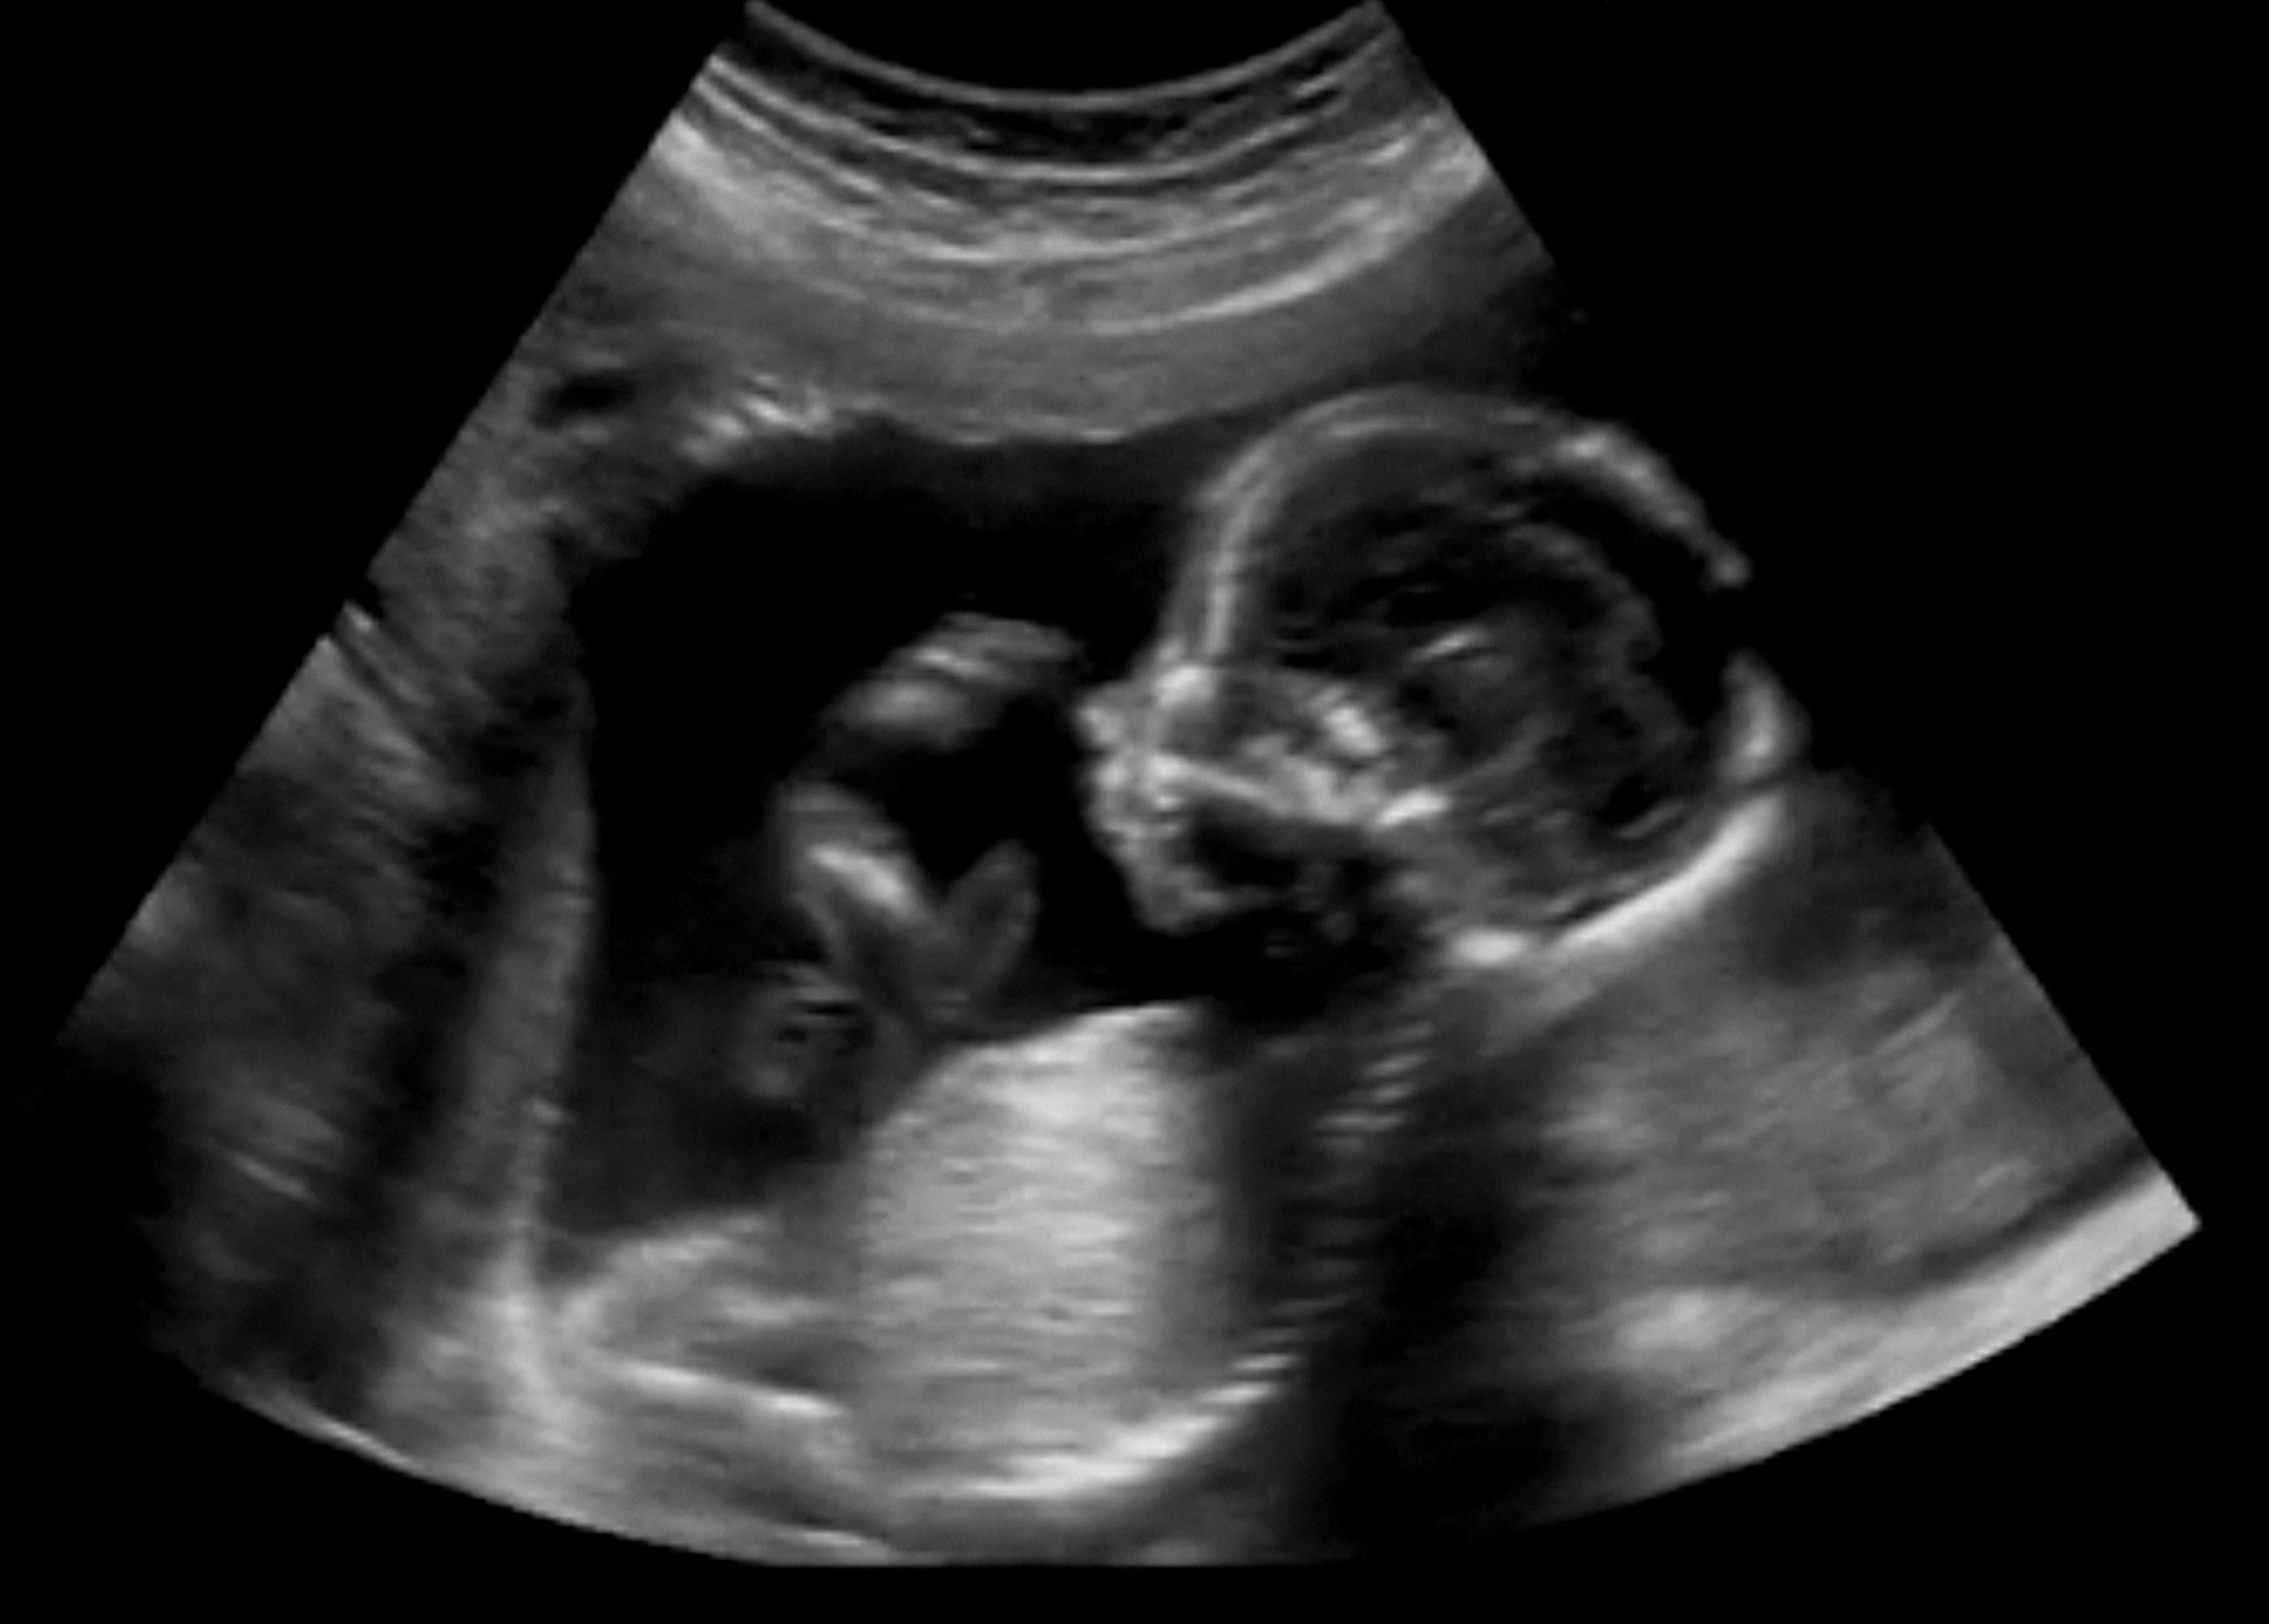

An ultrasound scan just for memorial purpose, it is NOT recommended.